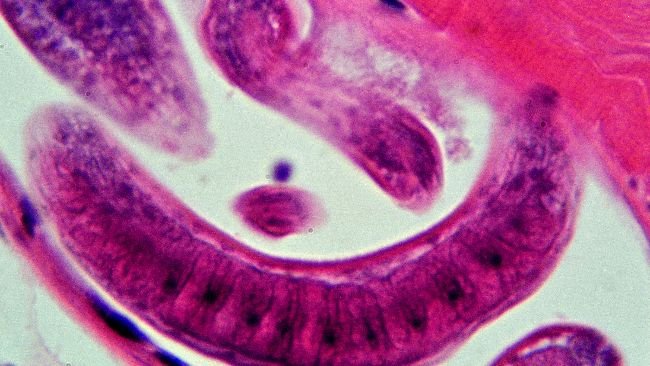

Ausencia de infección por Trichinella en cerdos comerciales en EE.UU.

Una investigación del USDA documenta la ausencia de infección por Trichinella en cerdos comerciales.